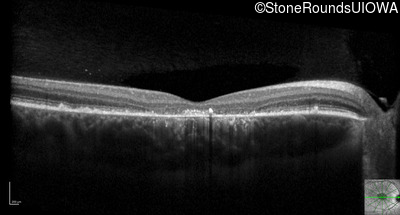

Optical Coherence Tomography - Left - 20/125 sc

Exemplar / OCT Stack

OCT Stack